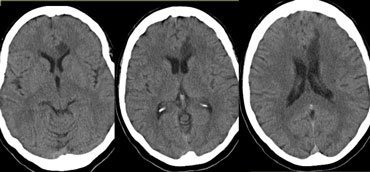

Stroke Syndrome:

In a right handed individual…

Transient hemiparesis Dysarthria Abulia or agitation inattentive, abulia, forgetful, agitation, psychosis

Bilateral caudate infarcts - from ACA distribution